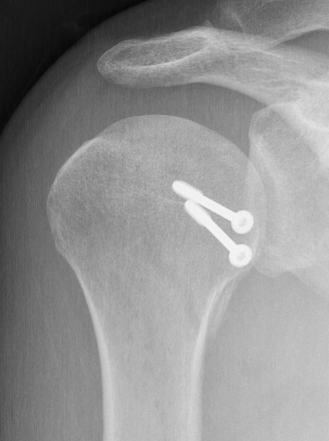

Subscapularis +/- Lesser tuberosity transfers

Indications

Defects 25%

Options

McLaughlin - subscapularis transfer into defect / makes defect extra-articular

Neer modification - lesser tuberosity + subscapularis transfer into defect

Results

- systematic review of modified McLauglin for locked posterior dislocation

- 9 studies and 97 shoulders

- reverse Hill Sachs 20 - 50%

- 100% union

- complication 1% (screw loosening)

- recurrent instability 2% (epileptic patients)